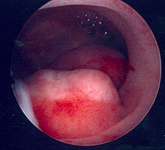

Multiple polyps are identified on hysteroscopic examination of the uterine cavity in this patient with persistent vaginal spotting

From the personal collection of Dr M.F. Mitwally and Dr R.J. Fischer; used with permission